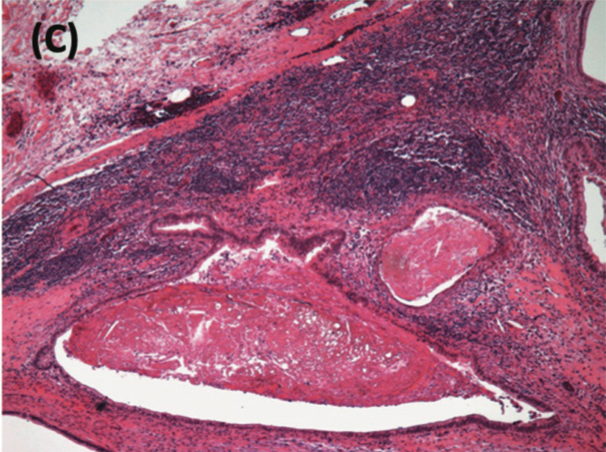

A bilateral nerve-sparing RPLND was performed without any surgical complications (Figure 2). The paracaval lymph nodes were resected, and pathological analysis was performed, which revealed a teratoma (Figure 2C). Further cytotoxic therapy was foregone, and the patient started 3-monthly surveillance per guideline recommendations.4

FIGURE 2. Bilateral Nerve-Sparing Retroperitoneal Lymph Node Dissection (RPLND) (A) Retroperitoneal view of the intraoperative site after nerve-sparing RPLND. (B) Surgical specimen of resected residual disease.

(C) H-E (Hematoxylin-eosin) stain from retroperitoneal lymph nodes showing numerous deposits of multicystic mature teratomas. The neoplasm is composed of cystic area lined by columnar and cuboidal epithelium, and other areas lined with squamous epithelium and keratinization, as well as focal mature cartilaginous tissue and fat.